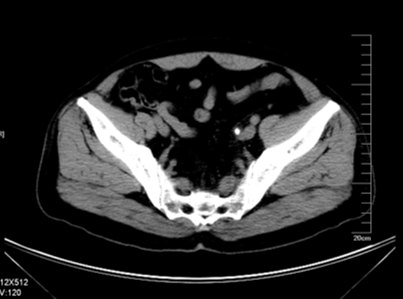

增强CT检查提示:左侧肾脏重度积水 皮质菲薄,几乎已无功能

左侧输尿管结石约1.5cm